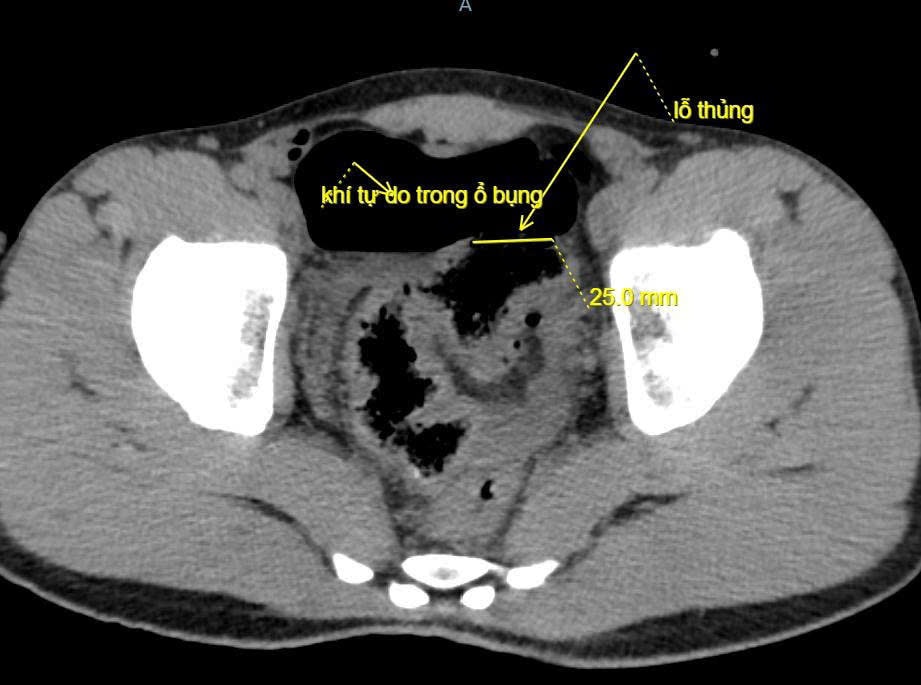

Kết quả chụp X-quang và CT scan ổ bụng cho thấy có nhiều khí tự do trong ổ bụng, nghi ngờ thủng tạng rỗng, bệnh nhân được chỉ định mổ cấp cứu ngay lập tức.

Ảnh chụp Cắt lớp vi tính ổ bụng. Ảnh: BVCC

Trong quá trình phẫu thuật, ê-kíp ghi nhận ổ bụng có khoảng 100ml máu và dịch bẩn, đoạn đại tràng sigma bị tổn thương dài 5cm, có lỗ thủng khoảng 2cm, mô xung quanh dập nát. Người bệnh được cắt lọc, khâu phục hồi đại tràng, làm sạch ổ bụng và đặt dẫn lưu.